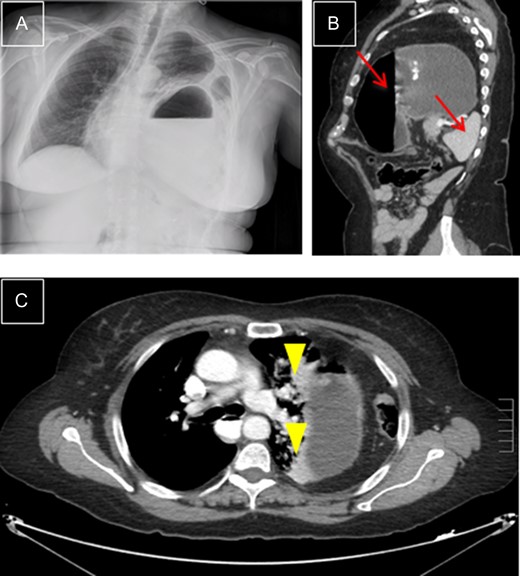

This is a 76-year-old male who came to the Emergency Department with intense periumbilical abdominal pain radiating to the back and vomiting. The patient underwent a right laparoscopic radical nephrectomy 18 days before. There were no complications during the procedure and post-operative period. Physical examination showed right basal hypoventilation with abdominal pain and tenderness in the right upper quadrant. A CT scan showed an orifice in the right diaphragm, through which intestinal loops passed into the thorax, which were dilated and with signs of ischemia (Fig. 1), image not present in the pre-operative CT. The patient underwent emergency surgery, via a right subcostal laparotomy. A diaphragmatic hernia ~6 cm in size was found in the right posterior costophrenic angle with a nonviable loop of ileum, reduced and resected after mobilization of the right hepatic lobe. The orifice was closed with interrupted tension-free stitches. Post-operative recovery was uneventful. One year after the surgery, the patient is asymptomatic and shows no signs of hernia recurrence.

Right diaphragmatic hernia. (A) Thoracic-abdominal CT angiography, sagittal cut, showing right posterior location. (B) Coronal cut: Ileal loop in supradiaphragmatic position (arrowhead). (C) Transverse cut: edges of hernial ring (arrows).